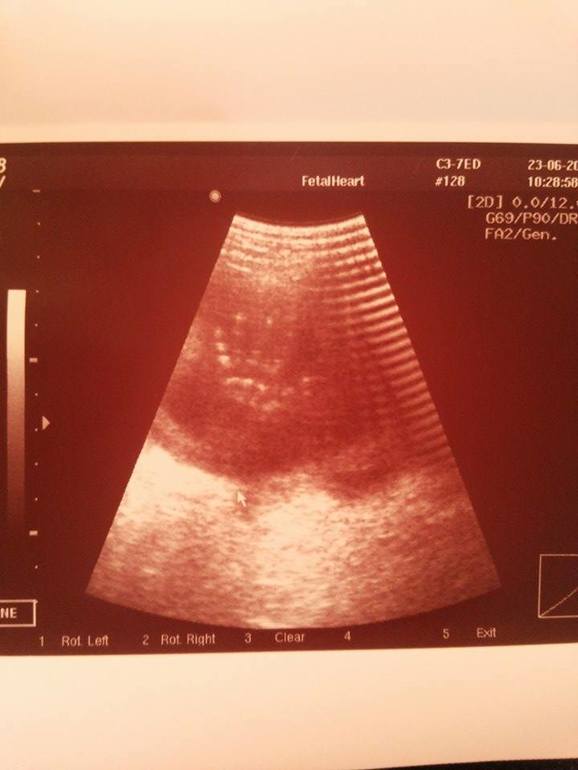

А это проказы моего малыша, ручка которого была сжата в кулак, и врач не могла посчитать его пальчики. Когда же он это услышал, то раскрыл ладонь и показал нам, что все у него в порядке, а заодно и передал привет)Воть)

спасибо всем большое) да он так долго махал ручкой, что мы успели и сфотографировать этот момент)))да...на снимке ладошка большая, а на самом деле мы маленькие еще))))